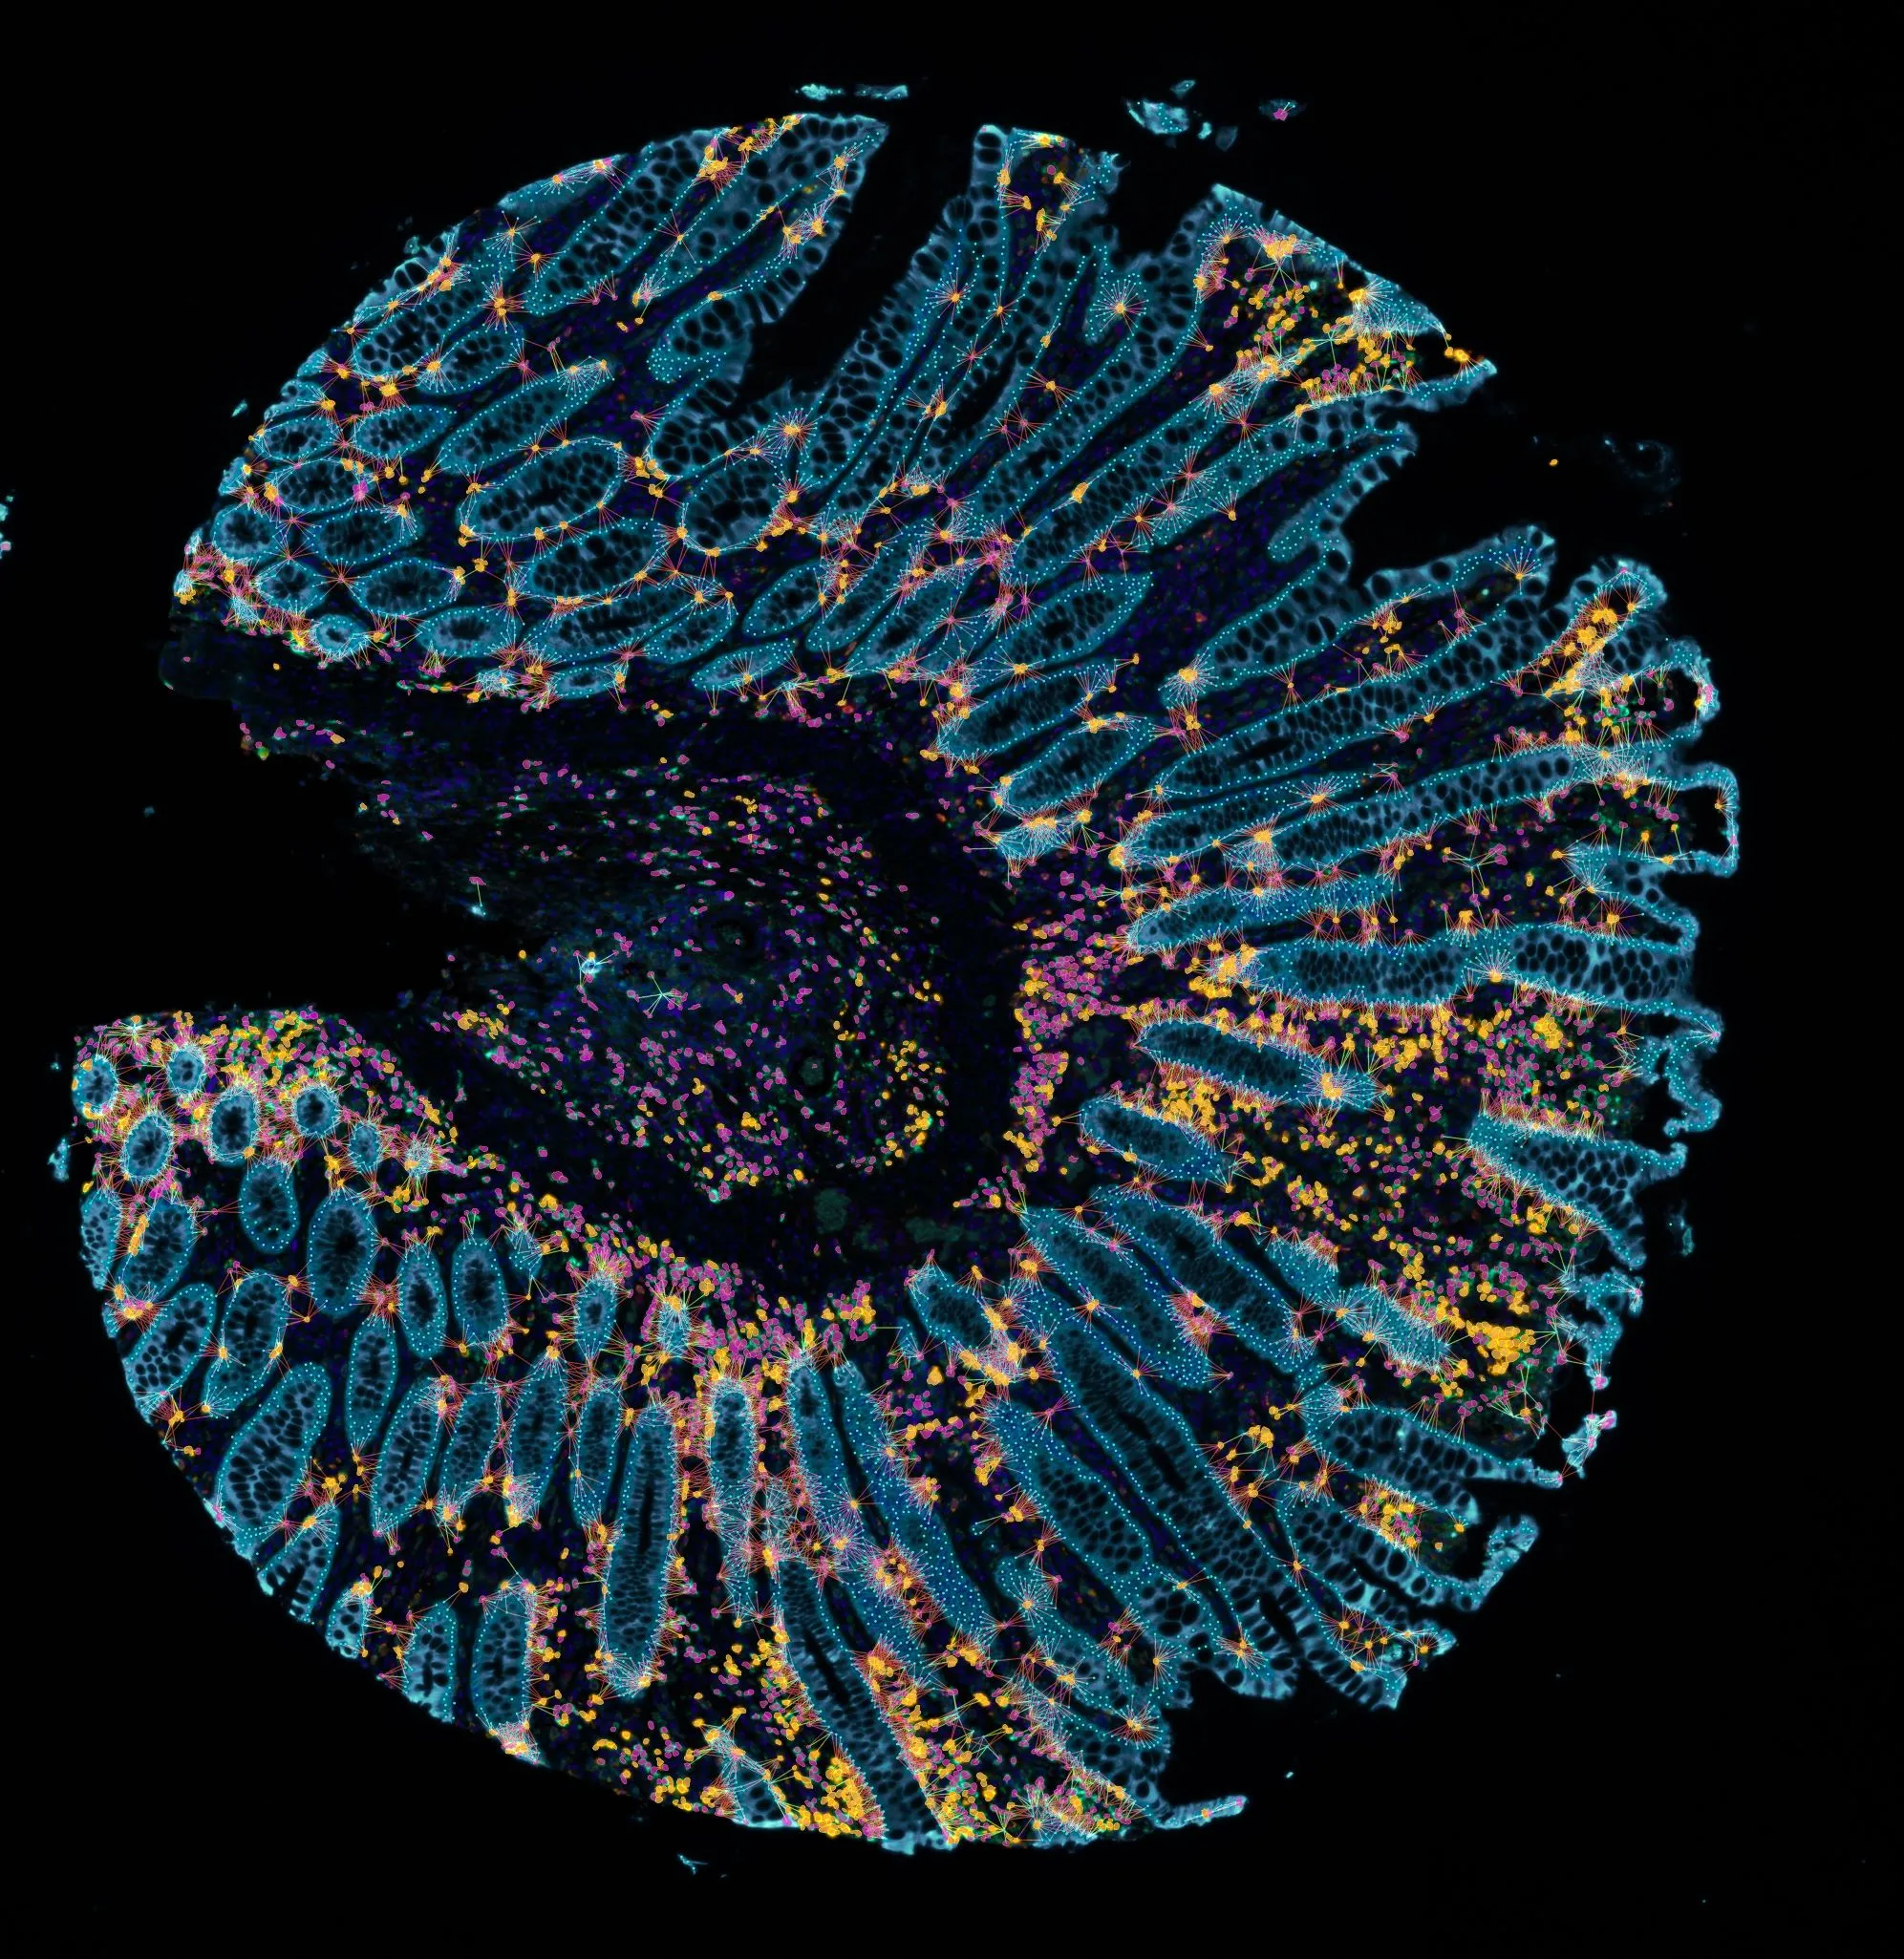

The image below shows a TMA core of an inflamed colon sample acquired with TissueFAXS Spectra (TissueGnostics), capable of multispectral imaging and spectral unmixing. The sample was stained for several markers: DAPI (nuclei), CD4 (T helper cells), PD1 (immune checkpoint molecule, participates in downregulating of the immune response), CD8 (cytotoxic T cells, CTLs), and CK (epithelial cell marker).

Figure 1. Spectral Unmixing.

An example of such an image is shown in Figure 6. CD4+ T cells are outlined in green contour (left) and CD8+ T cells in yellow contour (right) and each cell is connected to a CK+ cell in maximum 30 µm range visualized by red lines. In this example the distance of 30 µm between two cells will be considered as an interaction, but the range can be changed according to specific needs. Corresponding scattergrams report the number of interactions (e.g. number of CK cells in 30 µm range from a CD4+ or CD8+ T cell) grouped in ranges from 1-4, 5-8 or 9+ interactions per cell. This way, it can be determined that most cytotoxic CD8+ T cells (70% of all CD8+ T cells) have at least one interaction with a CK+ cell, and 37% of all CD8+ T cells interact with 9 or more CK+ epithelial cells. In this range the average interaction number reaches 15. For CD4+ helper T cells, only half of them have at least one interaction with a CK+ cell, and the proportion of cells is relatively equally distributed among different interaction ranges. On average, one CD4+ T cell is surrounded by four CK+ cells in 30 µm range, whereas one CD8+ T cell by seven CK+ cells, which may indicate that there could be some kind of attraction mechanism which specifically moves CD8+ T cells closer to CK+ cells.

Figure 6. Phenotype interactions.